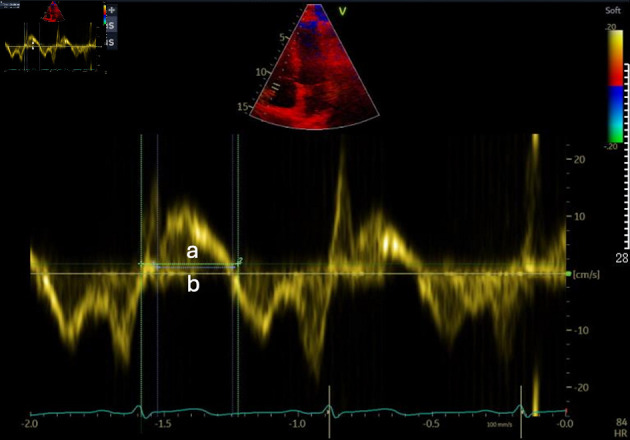

Results: The study found no significant differences in baseline demographic or clinical parameters between groups. Age was negatively correlated with FMD values, indicating decreased endothelial function with advancing age. The normal endothelial function group demonstrated better diastolic and systolic parameters and lower right ventricular Tei indices compared to the reduced function group. Additionally, there was a significant negative correlation between the right ventricular Tei index and FMD values.

Conclusions: Endothelial function is associated with right ventricular performance in patients with primary (essential) grade 1 systemic hypertension. Improved endothelial function is associated with better overall cardiac performance. Further studies with age-matched controls are necessary to confirm these findings and determine the independent effects of hypertension on cardiac function.